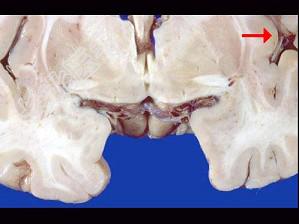

- 单项选择题如图箭头所示为大脑哪个部位 ( )

A、壳核

B、颞叶

C、尾状核

D、岛叶

E、海马